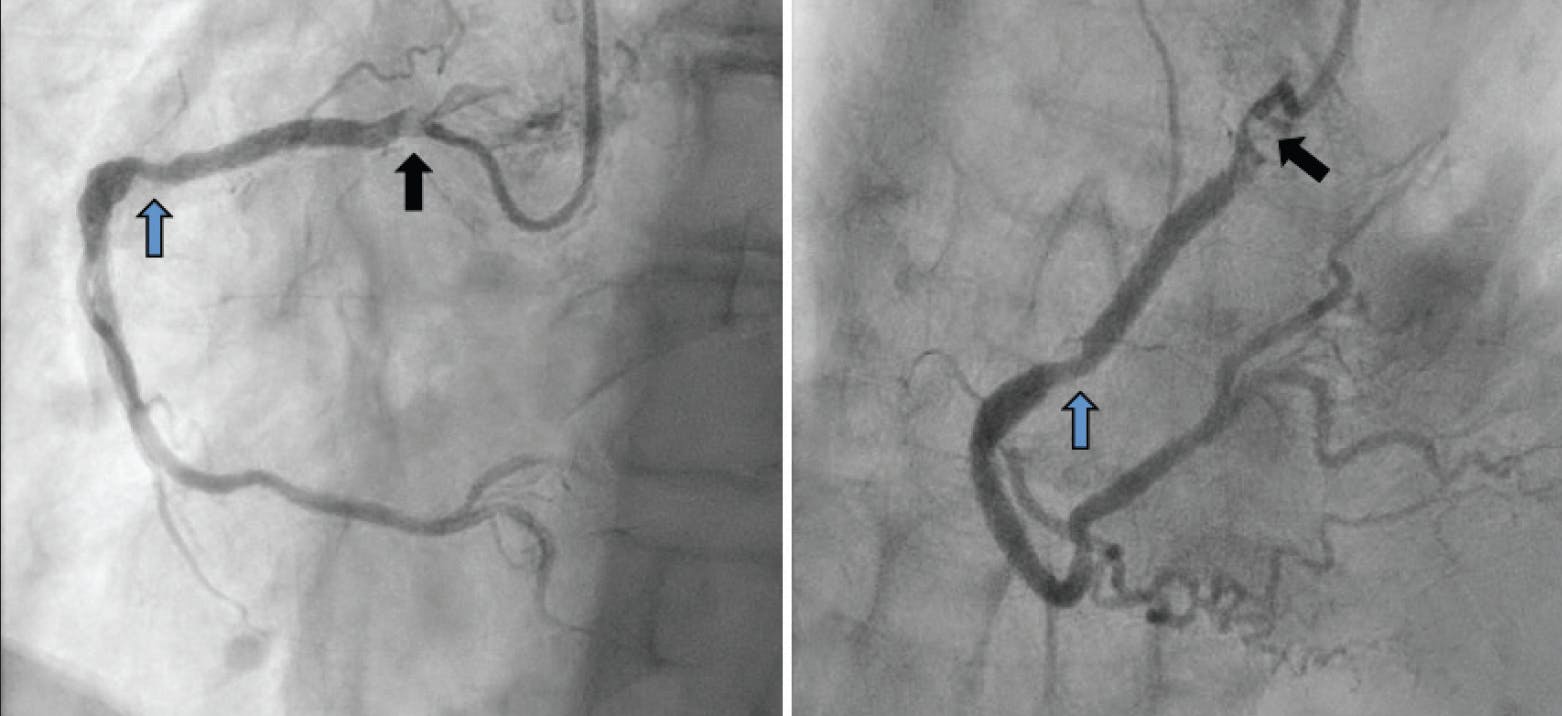

To facilitate calcific nodule plaque modification and lesion compliance softening, we treated the ostial and proximal stenosis with a 3.5-mm Shockwave intravascular lithotripsy balloon (Shockwave Medical), focusing all 120 shockwave pulses in the 20-mm de novo calcified nodular segment of the culprit stenosis (Figure 3A). We chose intravascular lithotripsy for plaque modification because of its unique mechanism of action to fracture the deep basilar structure of calcific nodules to improve compliance and facilitate adequate stent expansion when treating nodular calcium.23,24 The intravascular lithotripsy balloon initially had a substantial waist; however, after the 120 pulses, the artery appeared to expand completely at 8 atm of pressure on the final Shockwave inflation. Next, we predilated the in-stent restenosis segment with a 3.5- X 15-mm noncompliant balloon that did not yield completely. Therefore, we took a 3.5- X 10-mm AngioSculpt scoring balloon (Philips), inflated it to 22 atm, and performed cine angiography in multiple views to ensure adequate lesion expansion.

Figure 3. PCI execution with Shockwave pretreatment, aorto-ostial stenting, and Ostial FLASH stent flaring. To facilitate calcific nodule plaque modification and lesion compliance softening, we treated the ostial and proximal stenosis with a 3.5-mm Shockwave intravascular lithotripsy balloon focusing all 120 shockwave pulses in the 20-mm de novo calcified segment of the culprit stenosis (A). We placed a 3.5- X 32-mm Synergy Megatron high-radial-strength stent in the ostial and proximal vessel to treat the de novo segment that contained the large calcific nodule. In order to ensure adequate aorto-ostial lesion coverage, we purposefully placed the ostial Megatron stent into the aorta (B) with the plan to use an Ostial FLASH balloon to flare the stent to optimize aorto-ostial stent coverage and to ensure ease of arterial access in the event that future angiography and/or PCI were required. We inflated a 4-mm Ostial FLASH in the overhanging Megatron stent to flare the stent (C).

We similarly predilated the ostial and proximal RCA de novo culprit lesion with a high-pressure 3.5-mm AngioSculpt inflation at 22 atm, confirming complete expansion in orthogonal cine angiography views. We performed multiple orthogonal views of the balloon dilations to ensure that the eccentric calcified lesions expanded completely. After achieving adequate vessel preparation confirmed by 1:1-sized balloon expansion in multiple views, we moved forward to scaffold the artery with overlapping drug-eluting stents. We placed a 3.5- X 38-mm Xience drug-eluting stent (Abbott) in the mid-RCA and overlapped a 3.5- X 32-mm Synergy Megatron high-radial-strength stent (Boston Scientific Corporation) in the ostial and proximal vessel to treat the recoil-prone de novo segment that contained the large calcific nodule. To ensure adequate aorto-ostial lesion coverage, we purposefully placed the ostial Megatron stent into the aorta with the plan to use an Ostial FLASH balloon to flare the stent to optimize aorto-ostial stent coverage and to ensure ease of arterial access in the event that future angiography and/or PCI were required (Figure 3B). We inflated a 4-mm Ostial FLASH balloon in the overhanging Megatron stent to flare it and subsequently postdilated the distal stent with a 3.5-mm noncompliant balloon and postdilated the proximal and ostial stent with a 3.75-mm noncompliant balloon (Figure 3C).